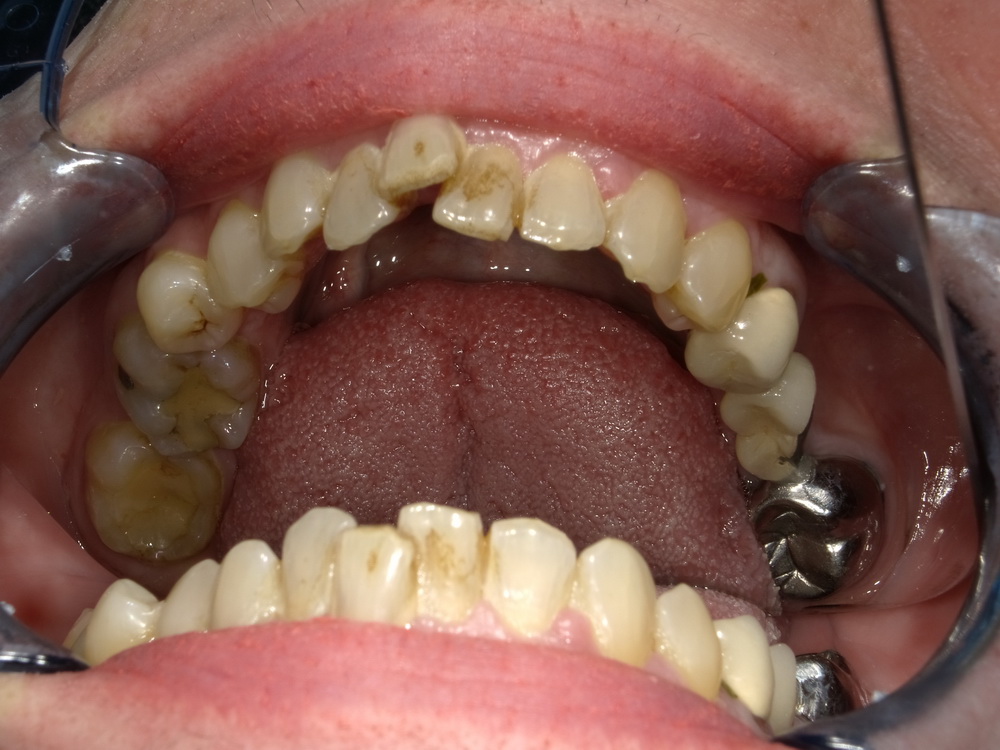

CMD-Patientin ausdem Schaumburger Land beginnt mir der Funktionstherapie

Nun soll es losgehen, was in den vergangenen Monaten systematisch vorbereitet wurde.

Es beginnt mit der Versorgung der Oberkieferseitenzähne mit Laborgefertigten Dauerprovisorien.

Das war der Zustand im September 2025.